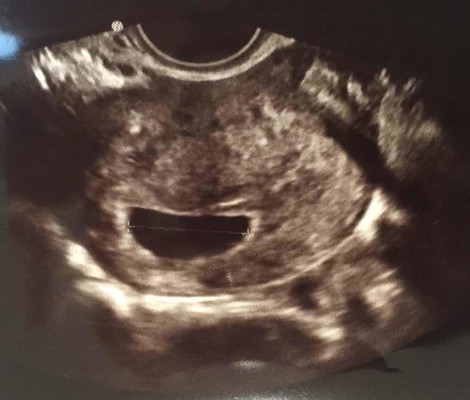

ใครเคยเป็นบ้างคะ ท้อง 8 สัปดาห์ ซาวด์ทางช่องคลอด เห็นแค่ถุงตั้งครรภ์ใหญ่เลย แต่ข้างในว่างเปล่า หมอบอกให้ขูดมดลูก รบกวนเล่าประสบการณ์หน่อยค่ะ ?? ขอบคุณค่ะ

เคยท้องลมเมื่อปีที่แล้ว ตอนนั้นได้ 8 week ไปอัตราซาวน์เจอแต่ถุงไข่แดงแต่ไม่เจอตัวเด็ก หมอเลยให้ขูดมดลูกค่ะ ปล.เราไปหาหมอมา 2 ที่นะคะ ทั้ง 2 ที่ตอบเหมือนกันว่าเราท้องลมให้ขูดมดลูกค่ะ